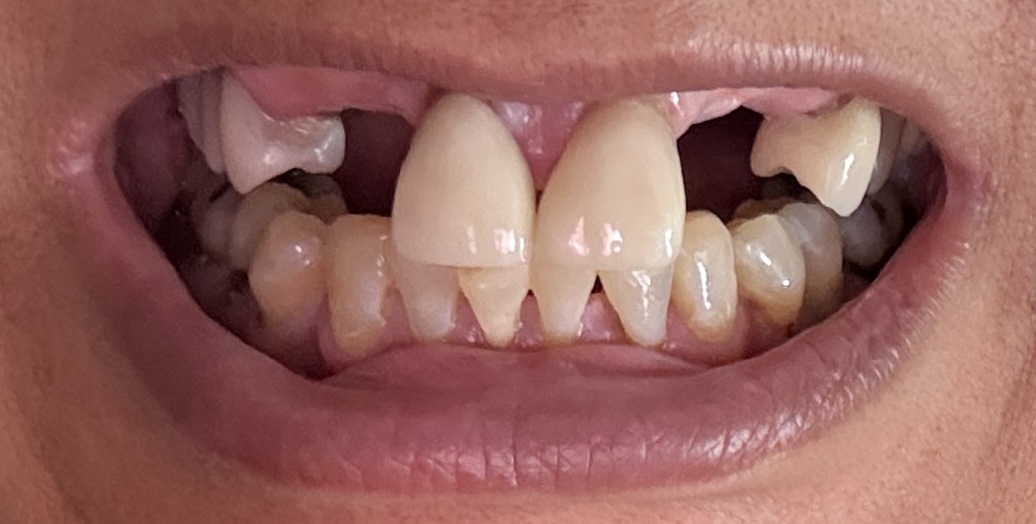

Dental Auction No. 11561: Several extractions and All-on-4 Top and bottom arches

Overall information (upper arch)

12,13,14 have had root canals in past and now have quite a bit movement. 2-5 have all had root canals in past and now the crowns are breaking down.

Overall information (lower arch)

Overall, all of my gums have receded and most of the bottom teeth are exposed w/ some roots and there are many cavities.